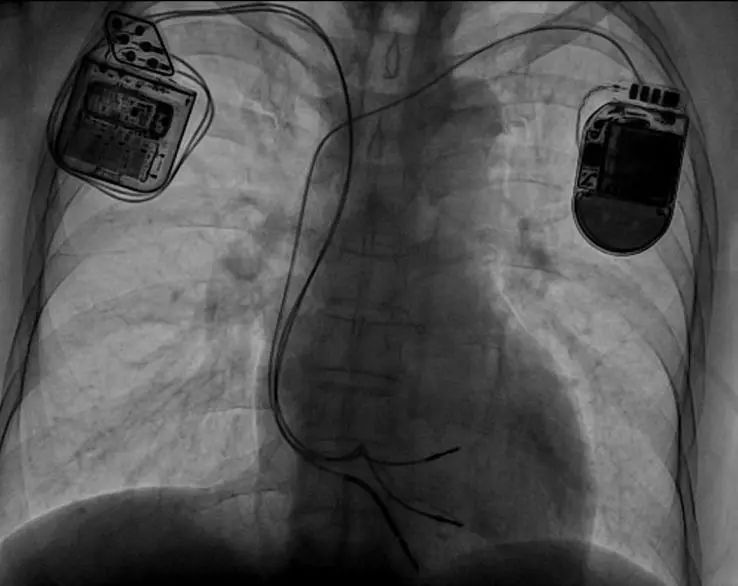

术后影像

术中两位术者从左、右两侧同时进行静脉穿刺及制作囊袋,之后先从左侧完成心尖部除颤电极的植入,随后从右侧将两根主动起搏电极置于右室间隔部。术中测试除颤电极阻抗685Ω,阈值0.4V,R波大于22.6mV;两根起搏电极的起搏阈值均为0.6V,感知均大于15mV,起搏阻抗均低于800Ω,表明电极准确植入在健康心肌上。交叉感知测试分别在CCM脉冲序列延迟为30ms和80ms时均无ICD交叉感知。5G远程技术支持下的CCM联合ICD一站式手术顺利完成,耗时不到两小时。